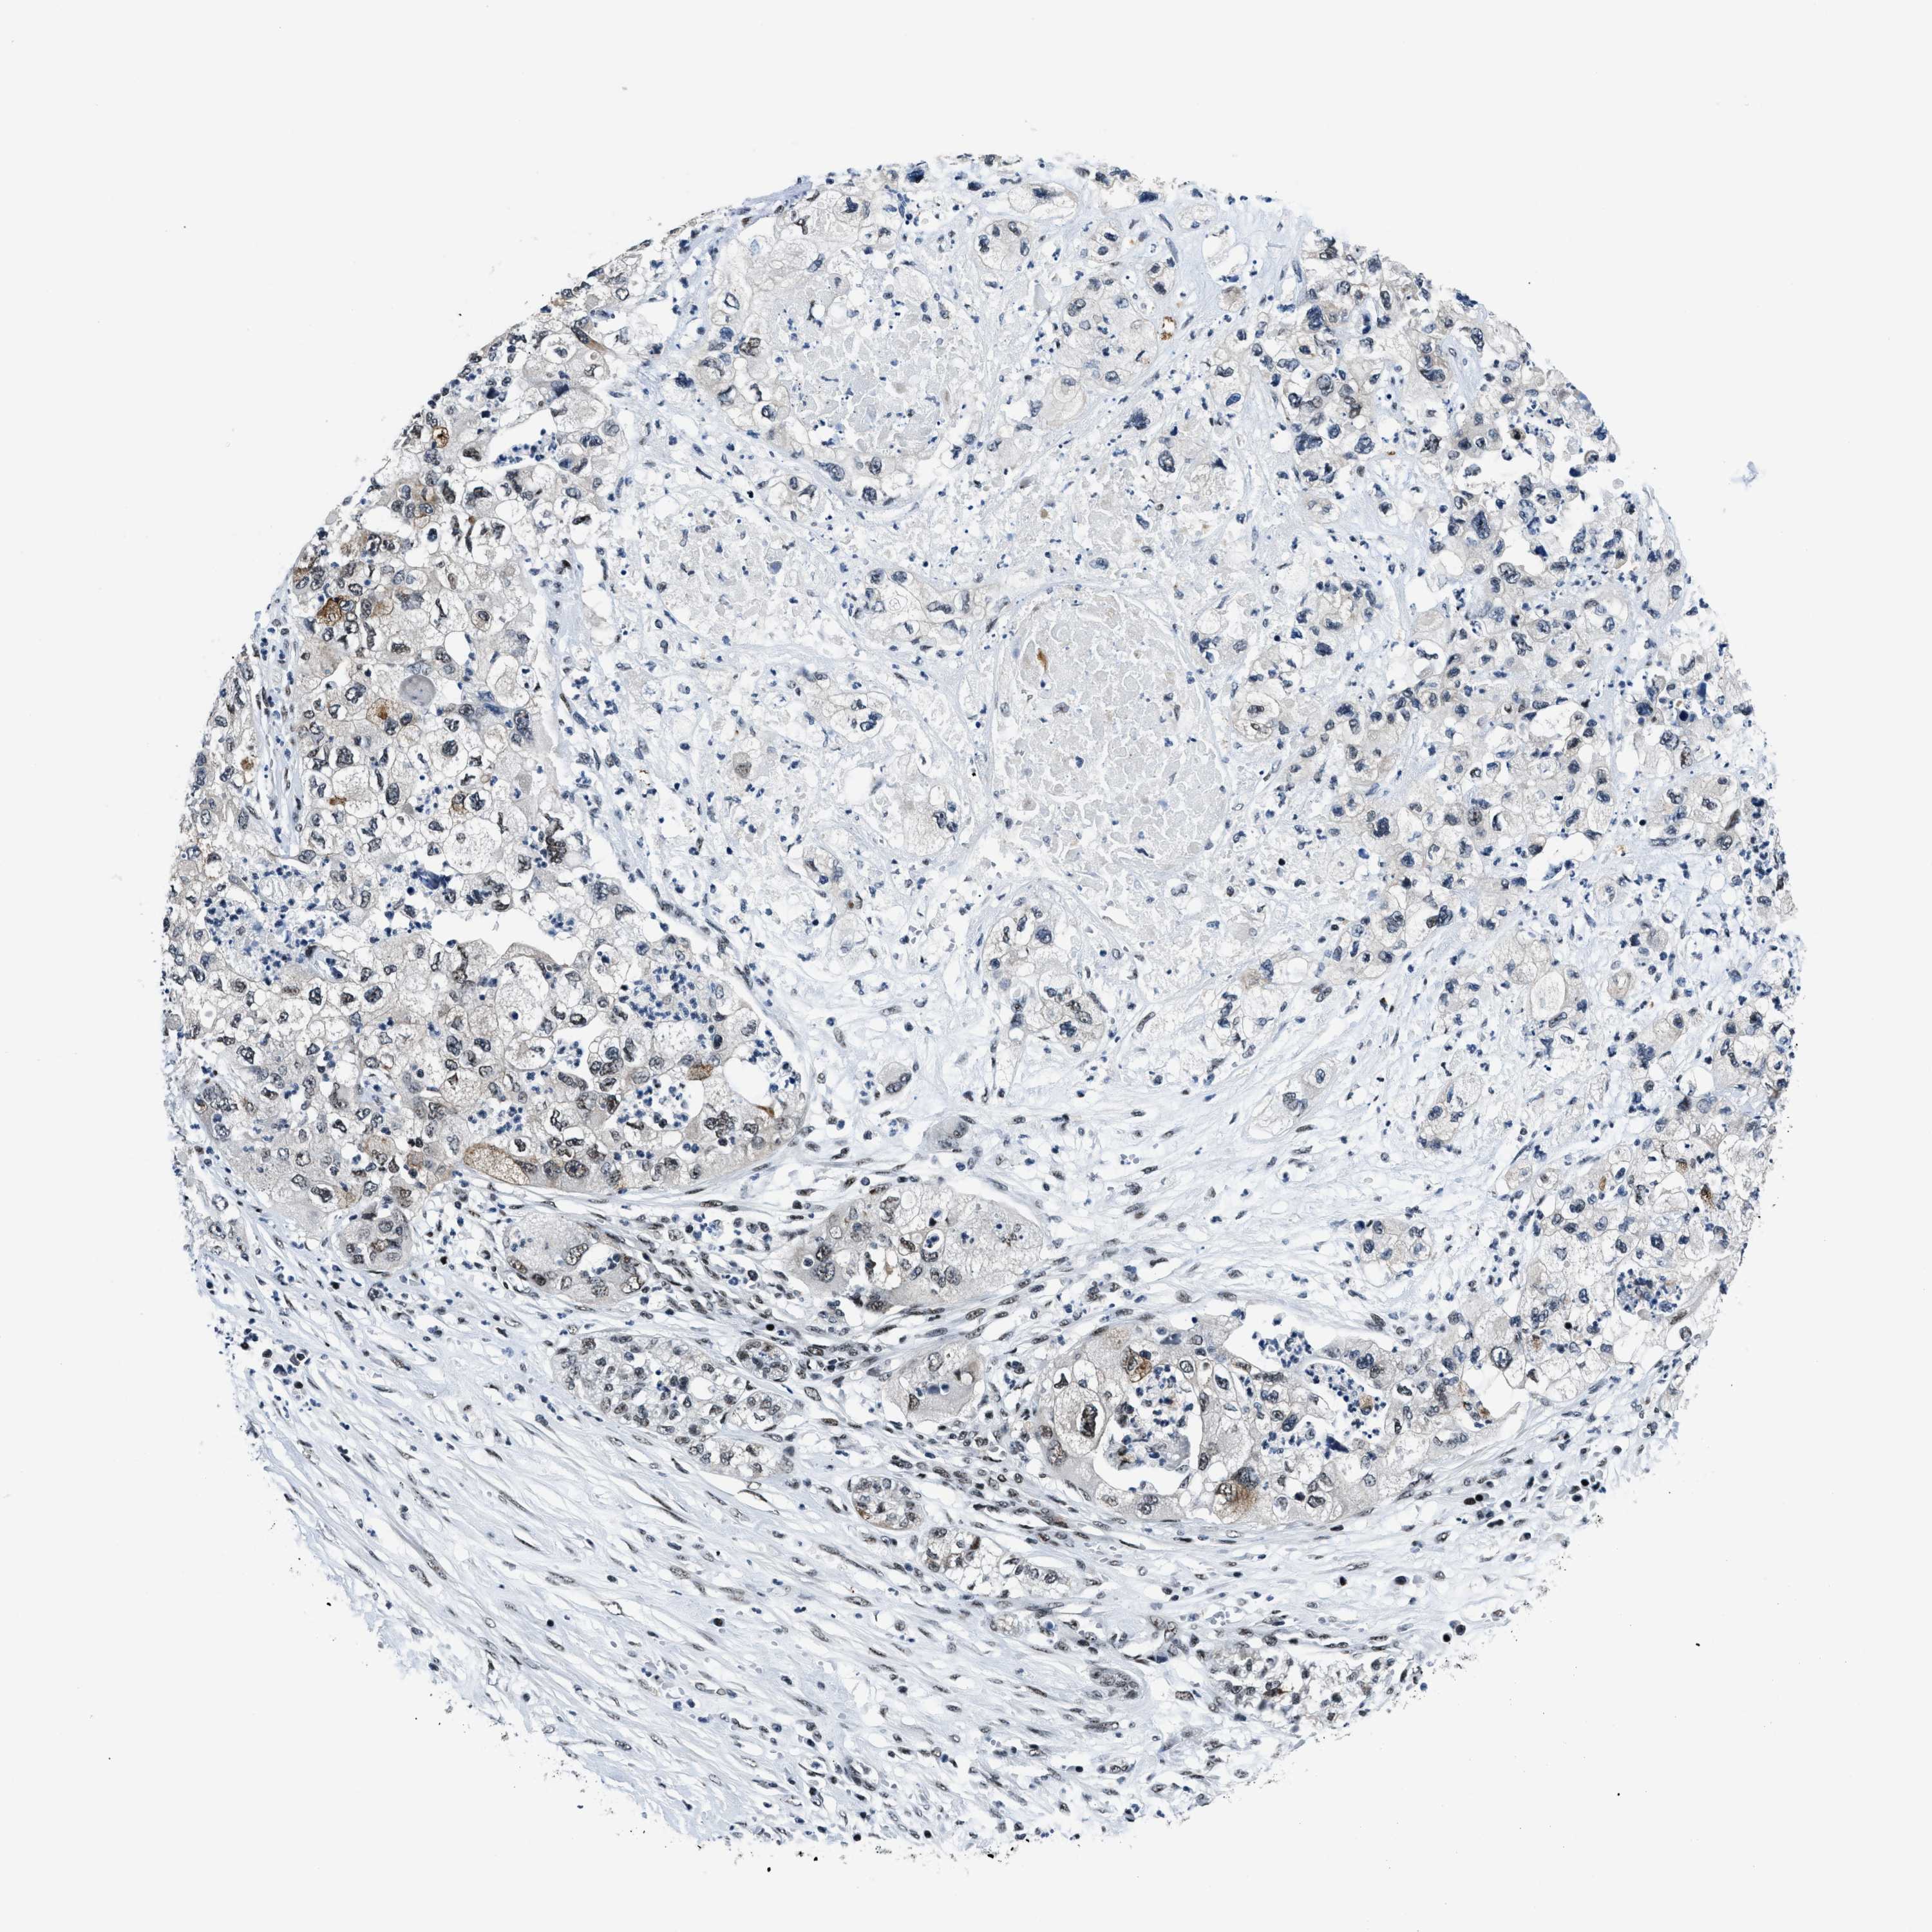

PANCREATIC CANCER - Protein expressioni

A mouse-over function shows sample information and annotation data. Click on an image to view it in a full screen mode. Samples can be filtered based on level of antibody staining by selecting one or several of the following categories: high, medium, low and not detected. The assay and annotation is described here.

Note that samples used for immunohistochemistry by the Human Protein Atlas do not correspond to samples in the TCGA dataset.

Antibody stainingi

Antibody staining in the annotated cell types in the current human tissue is reported as not detected, low, medium, or high, based on conventional immunohistochemistry profiling in selected tissues. This score is based on the combination of the staining intensity and fraction of stained cells.

Each image is clickable and will lead to virtual microscopy that enables deeper exploration of all samples and also displays staining intensity scores, fraction scores and subcellular localization as well as patient and tissue information for each sample.

Antibody HPA018248

Antibody HPA019127

Antibody CAB009196

Staining

High

Medium

Low

Not detected

Adenocarcinoma, NOS

Adenocarcinoma, metastatic, NOS